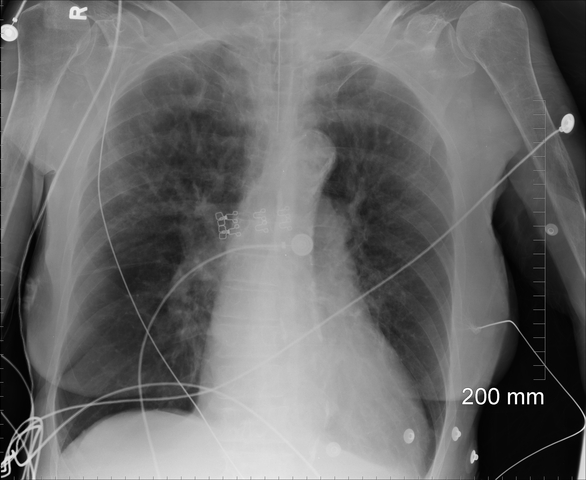

Found unresponsive by son. Intubated in field. Vent Settings A/C with a VT of 5 ml/kg, RR of 20 bpm, PEEP of 5cmH2O, and an FiO2 of 1.0. CXR showed pulmonary vascular congestion and pulmonary edema. Breathing treatments ordered. ABG revealed a partially compensated respiratory acidosis with excessively corrected hyperoxemia. Labs revealed a normal WBC count and low potassium levels.

CXR revealed pulmonary edema, Labs low potassium levels and a normal WBC count. ABG revealed a uncompensated metabolic alkalosis with mild hypoxemia. Went from a respiratory to a metabolic issue.

• Pulmonary Vascular Congestion

CXR revealed a pulmonary vascular congestion. ABGS's revealed a uncompensated metabolic alkalosis. RR decreased to 8 bpm. FiO2 at .30. Labs revealed low potassium levels and elevated WBC count. Antibiotics ordered.